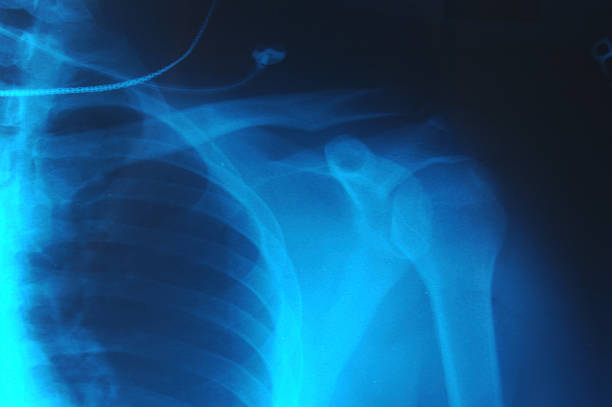

A broken collarbone (also known as the clavicle) is a common sports injury sustained by children at play. Some babies are even born with an injured collarbone as a result of delivery. That’s because a child’s collarbone doesn’t harden until they reach adulthood and can easily crack due to a fall or direct blow. With athletes, the force of a fall can transmit from the elbow and shoulder to the collarbone, resulting in a fracture.

Treatment for a Broken Collarbone

When you sustain a broken collarbone, the signs are obvious:

- Your shoulder will sag downward and forward, and the pain will be too intense for you to lift your arm.

- You will feel a grinding sensation if you attempt to raise your arm.

- You might notice a bump over the fractured area as a piece of bone pushes the skin upward.

Despite these symptoms, surgery is rarely necessary for a broken collarbone. Instead, the fracture tends to heal with conservative treatment measures, such as:

- Immobilization of the arm. A child typically wears a sling for up to four weeks, whereas an adult wears one for up to eight weeks.

- Pain management with nonsteroidal anti-inflammatory drugs (NSAIDs), such as acetaminophen or ibuprofen.

- Physical therapy in the form of a range of motion and strengthening exercises once the pain subsides and the fracture heals. However, you should not resume sports activities or overhead-reaching motions until shoulder strength is completely restored.